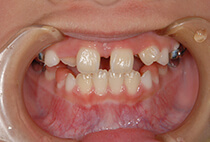

小学2年生の終わり、

「将来は外科矯正が必要」と言われた受け口の女の子。

小学生の成長力を最大限に生かすため、

上顎の成長促進・過蓋咬合の改善・機能訓練を同時にスタートしました。

1年後(小3 → 小4)

かみ合わせもお顔立ちも大きく改善。

その後も機能訓練×かみ合わせの維持をコツコツ継続。

診断の結果は、以下が原因の骨格性反対咬合。

反対咬合でよくあるケースです。

治療方法は、小さな上顎の成長誘導。

急速拡大装置と前方けん引装置を使用します。

成長のピークに合わせて上顎をもう一度拡大し、前歯のかみ合わせをさらに安定化。

成長期の波に合わせることで、より調和の取れた横顔へ。

治療開始から6年後。

治療終了後2年経っても、安定したかみ合わせと自然な横顔をキープ。

2年生で外科矯正と言われた受け口も、4年生になる頃にはすでに「バランスの良いお顔立ち」に。のびのびと成長期を過ごすことができました。